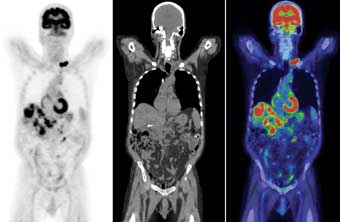

PET SCAN

After that eventful start to the morning, we went downtown for the PET Scan. As they ordered, I had been fasting since bedtime the night before and was only allowed to have water. By the time we arrived at 7am, I was already starving!

They took us back pretty quick. Unfortunately, Luis was not able to join me for any part of the somewhat lengthy, very boring process. But everything went very smoothly.

The medical technician pricked my fingers and did a blood sugar test. 96. He said that’s all good, and I’m always happy these days to get any test, however minor, that is deemed all good.

Next was the part where they inject me with radioactive sugar. This came in through the arm. I took a quick pre-IV photo… I guess I better get used to that view! My arms are starting to look like I’m a heroin addict as many times as I’ve been poked the last couple weeks.

I didn’t notice any sensations from the radioactive sugar that I had read about. It could have been saline for all I would have known otherwise.

After that, I had to sit alone in a room on a recliner for an hour while the radioactive sugar circulated through my body. I spent the time texting with Luis, family and friends – and also marveling at some better than average fantasy racing numbers from the previous day. I also was watching the local news on several stations, but there was only one topic they reported on: BRIDGE TOLLS START TODAY!

After they felt like I’d done enough circulating, they took me back to the scanner. It looks like a standard CT Scanner, and it might very well be. I had to lie perfectly still, on my back, with my arms stretched out over my head – for 30 minutes! No moving, eyes closed, no music, just silence.

It was pretty boring but 100% painless, so I’m very okay with it. I’m not sure if I fell completely asleep during the scan, but I kept having this scary dream that Marco was wandering out into the streets, but there was nothing I could do about it because I was stuck in this big tube!

At the time of posting this, I am still radioactive. The last thing they said to me when I left: Don’t go around any pregnant women or children today. You’ll be radioactive for the next 12 hours. That’s comforting.